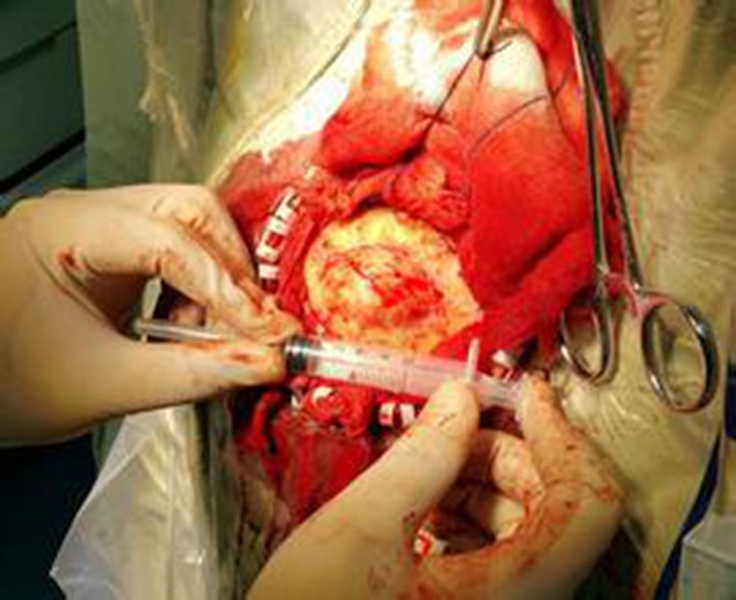

幼兒頸部手術煙霧病

A:煙霧病目前有兩種手術方式,分別是血管搭橋手術和血管貼敷手術。血管搭橋手術是將顳淺動脈進行剝離,然後與大腦中動脈進行吻合搭橋。而血管貼敷手術是將顳淺動脈剝離後貼敷到腦的表面上。通過這兩種手術方式,主要的起到的作用是建立新的側枝循環,從而供應腦……

A:煙霧病的主要手術方式是進行顳淺動脈搭橋手術或者貼敷手術,這種手術是需要進行全身麻醉的,因此做完手術後需要臥床,並且密切觀察病情變化。如果術後恢復順利,那手術後兩三天就可以開始下床活動,早下地能夠起到改善下肢循環的作用,能夠預防出現下肢的深靜……